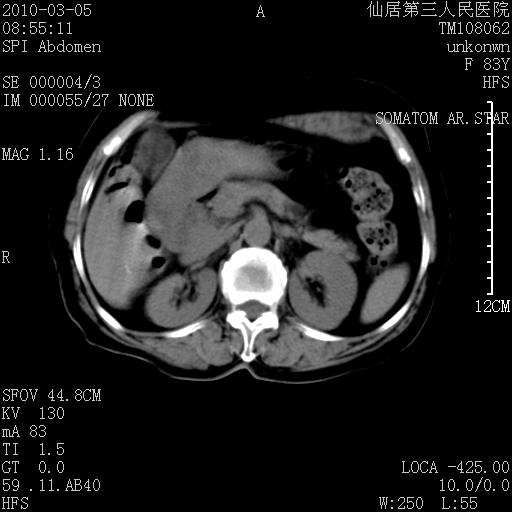

标题: CT24879:腹直肌病变。在线等。

女性,83y,腹痛一周。

考虑左侧腹直肌血肿,肿瘤性病变待排。

增强看看,mfh可能性大,次之可考虑血肿、bfh、转移瘤、神经纤维瘤、侵袭性韧带样纤维瘤等。肝内钙化灶,右肾结石。

血肿,纤维瘤,子宫内膜异位都有可能。